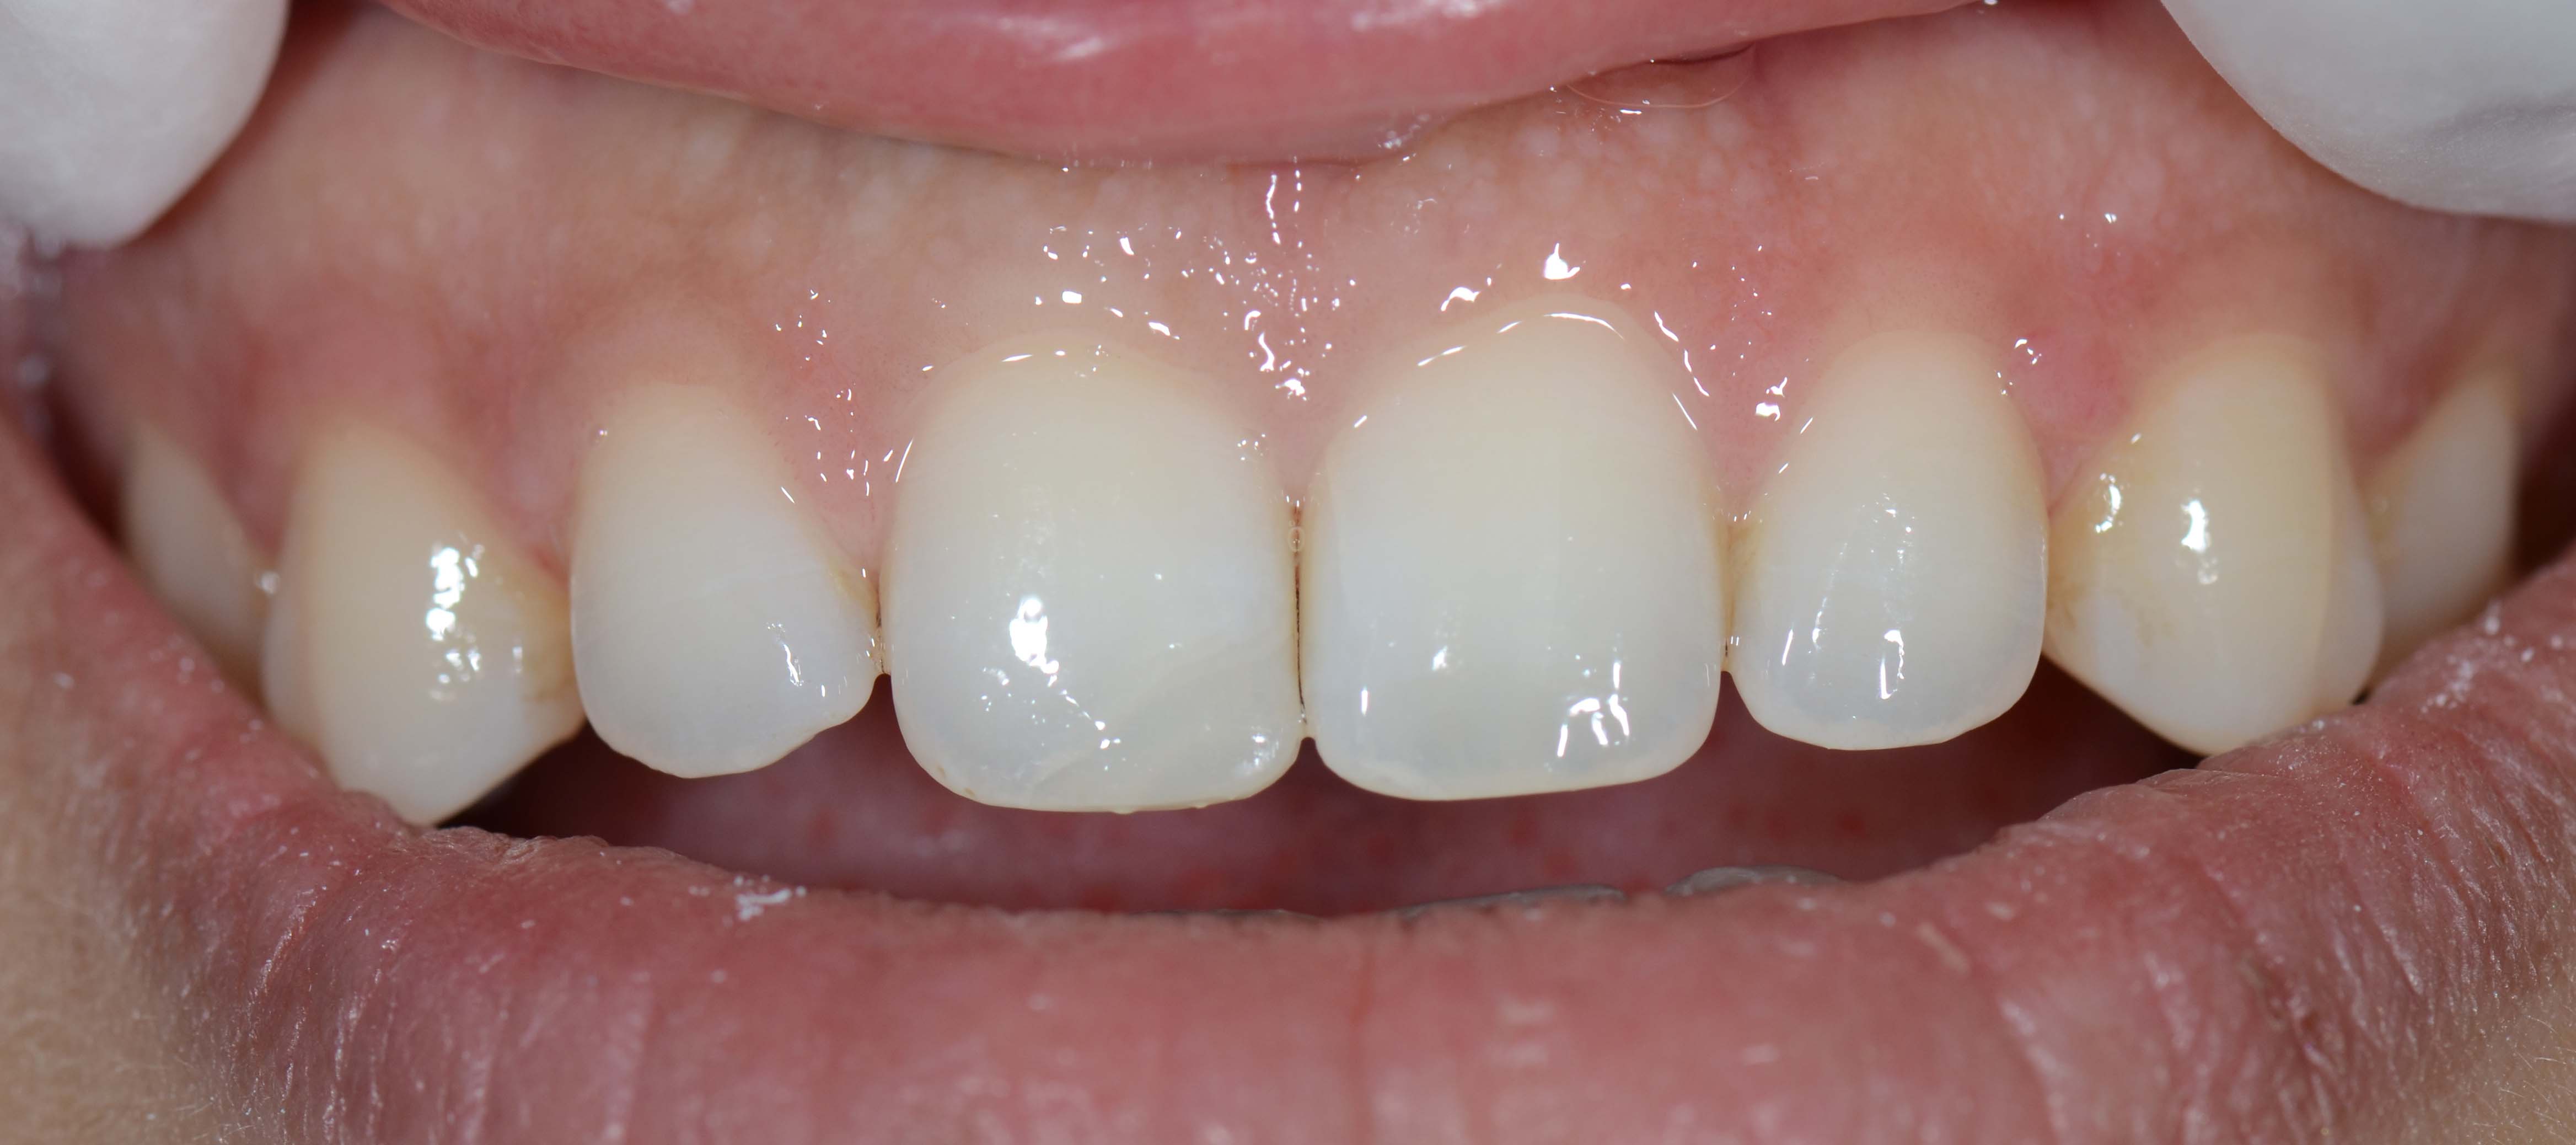

3. Fotografias